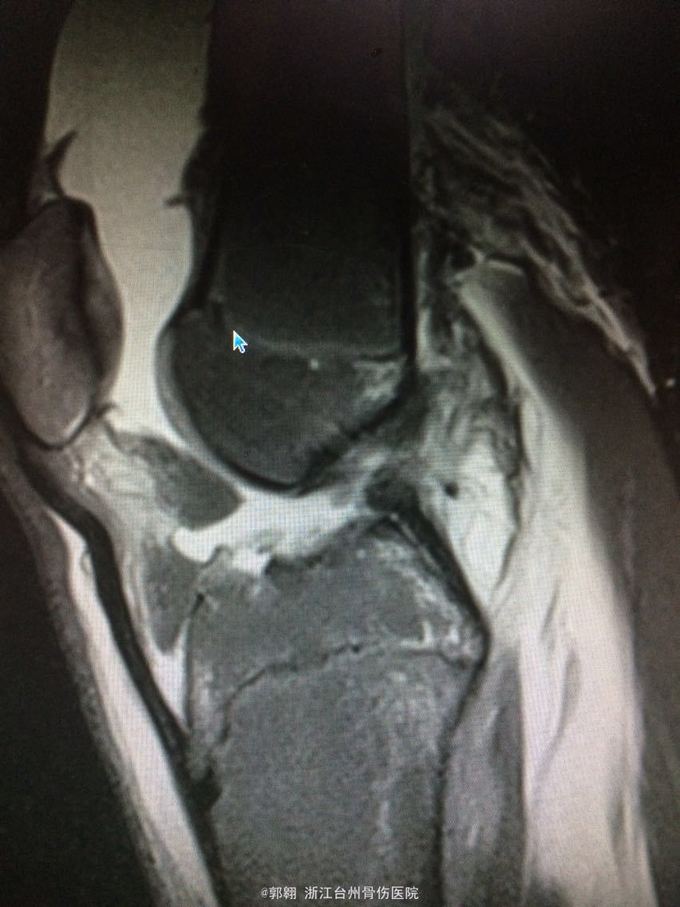

右膝关节跑步摔伤疼痛功能障碍3小时 病史:患者15岁 上体育课时跑步摔倒致右膝关节畸形疼痛 功能障碍,由老师送至医院就诊。

查体:右膝关节及小腿上段肿胀明显,张力较大,压痛位于内侧副韧带股骨处和膝关节外侧,膝关节波动感,浮髌试验阳性、扳膝试验阳性、抽屉试验阳性、Lachman阳性、膝关节屈伸活动因疼痛而障碍,足背动脉波动良好。 MRI:右膝关节股骨内髁骨折 胫骨平台外侧缘骨折

诊断:右膝关节内侧副韧带撕裂 前交叉韧带损伤 股骨内侧髁骨折胫骨平台外侧缘骨折 腓肠肌肌肉拉伤 处理:制动 支具托固定 冰敷 退肿止血药物治疗